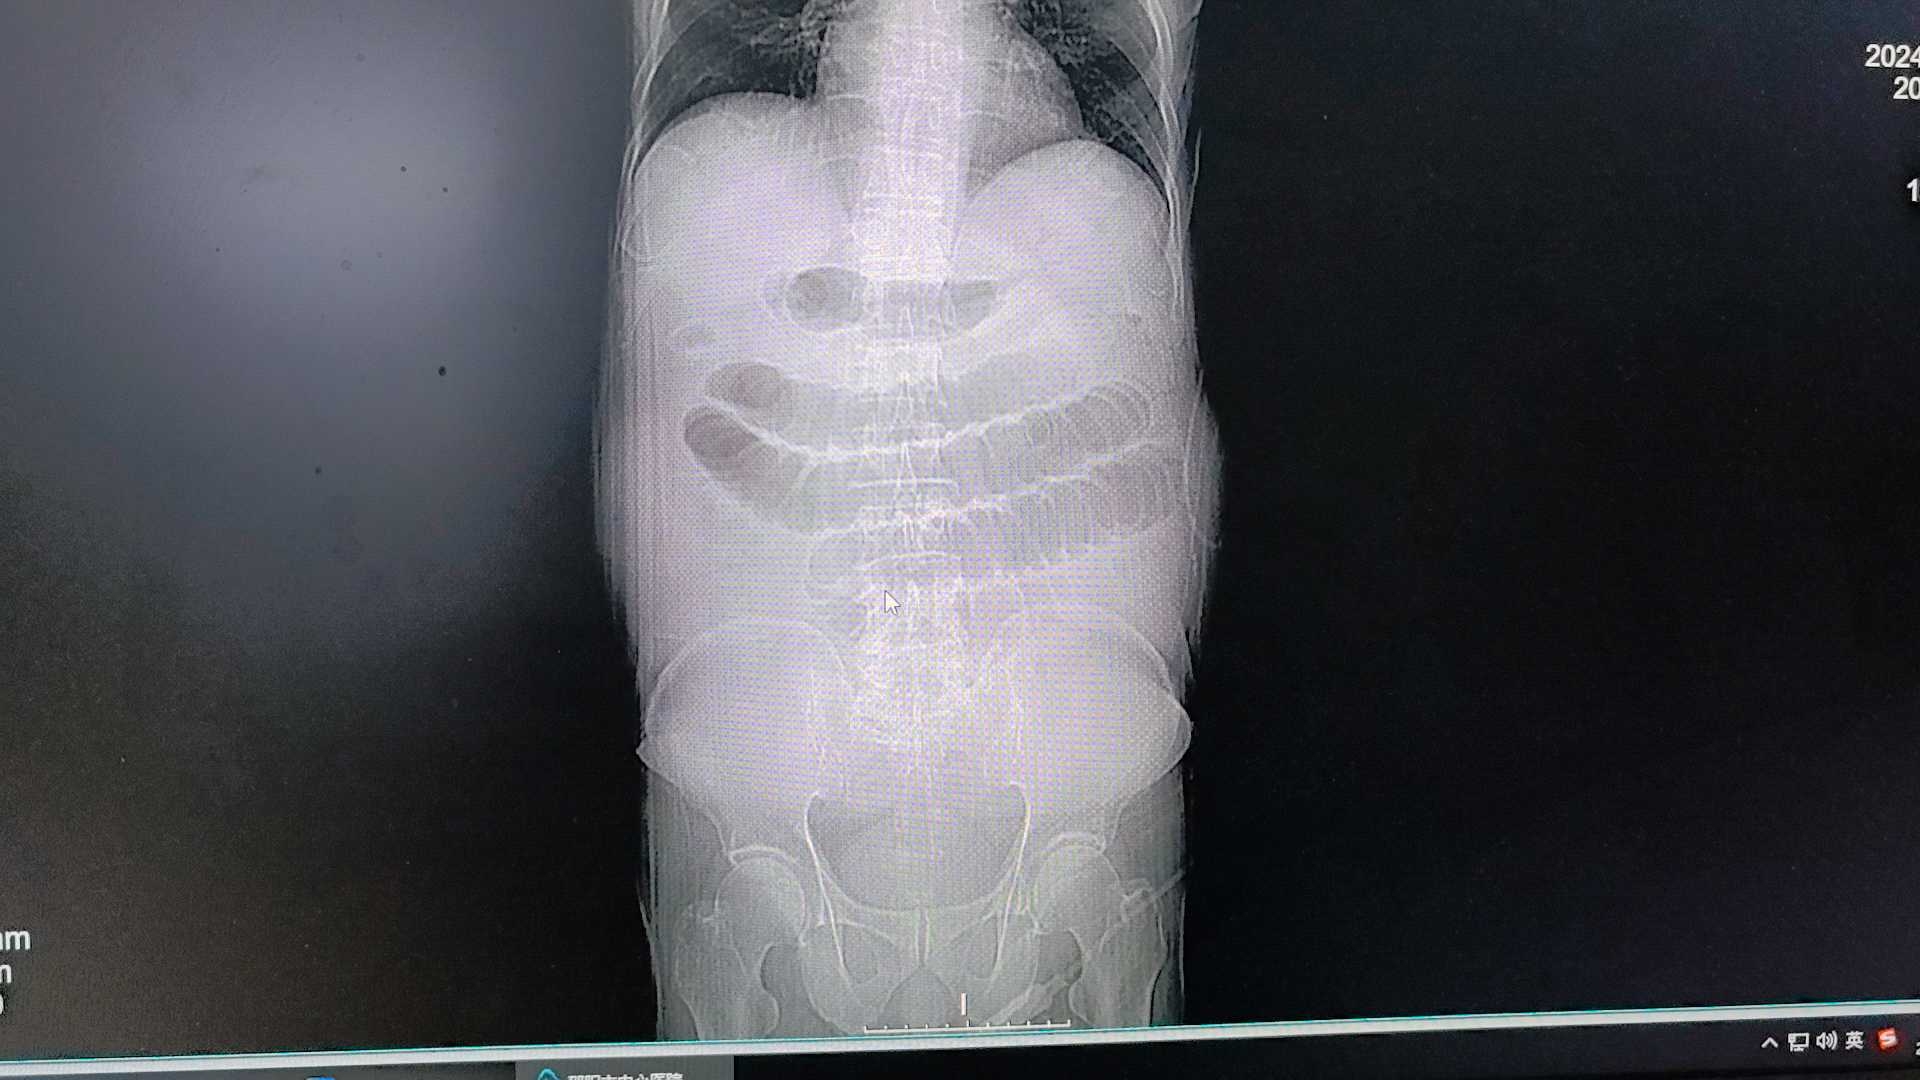

【检查】:入院CT

第二天腹痛加重,复查CT: